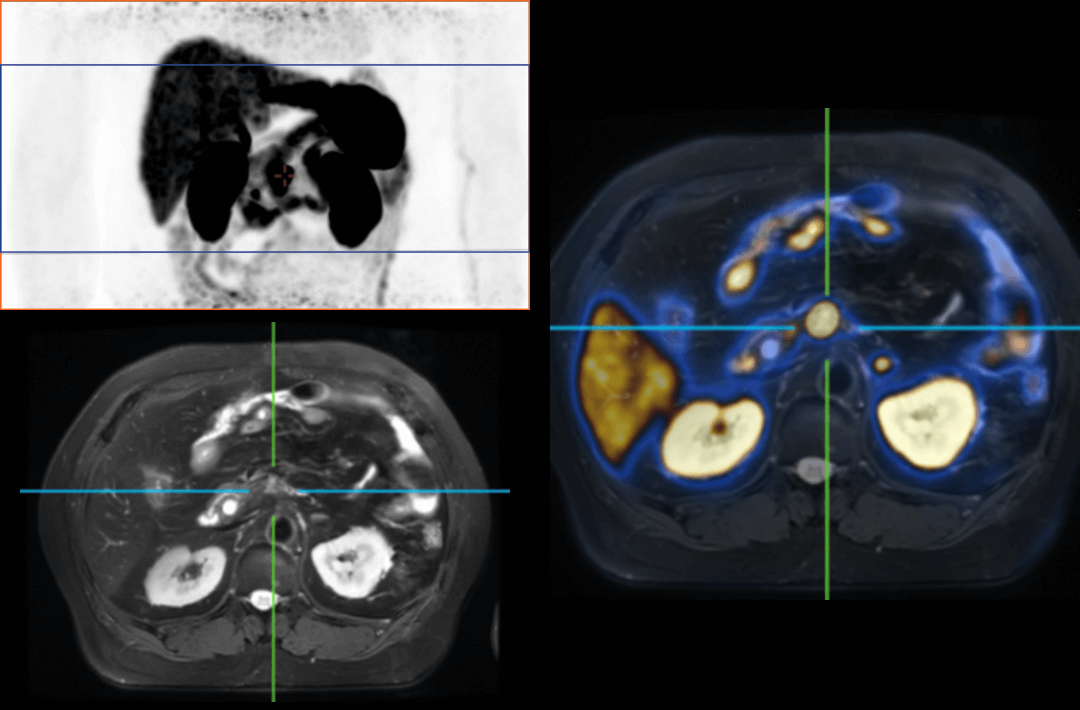

Compared with the conventional PET system with AFOV ranging between 20cm and 25cm, the 32cm long AFOV not only improves the sensitivity of the system, but also basically covers main organs of the whole body and the regional lymphatic system where metastasis may occur, and makes it possible to realize cancer TN staging in one bed position.

Traditionally, a PET/MR scan of a tumor patient takes about 35 to 50 minutes. The long AFOV can further optimize the PET/MR tumor scanning scheme. In other words, it can optimize the decision about whether to scan the whole body based on whether the tumor patient has regional lymphatic metastasis after regional PET/MR scan, potentially saving scan time for patients without metastasis.

In August 2019, Peking Cancer Hospital introduced United Imaging Healthcare's integrated PET/MR to make an in-depth exploration and optimization of cancer TNM staging under long AFOV. More than 500 examples of scanning various organs proved that long AFOV PET/MR could greatly increase the scan range over one bed position and improve the efficiency of cancer TNM staging.

The following are the cases of optimized TNM staging of breast cancer, esophageal cancer, prostate cancer and other diseases under the long axial field of "spatio-temporal integration" ULTRA-clear TOF PET/MR.  Thanks to Capital Medical University Xuanwu Medical Treatment for providing the image.